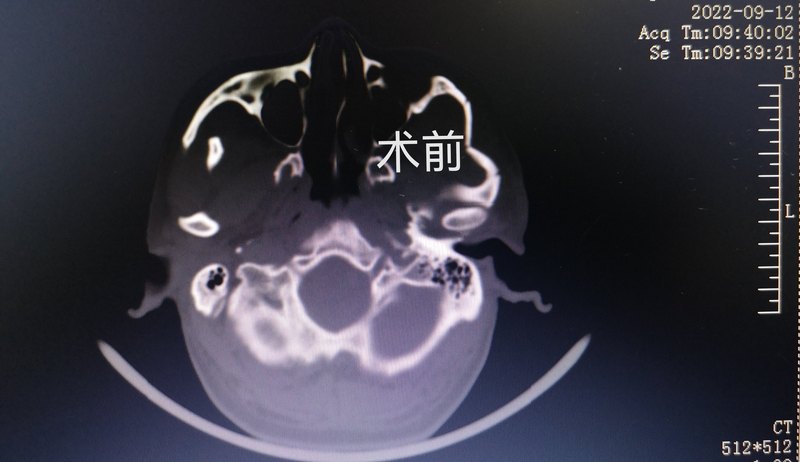

顴骨顴弓骨折的精準切開解剖復(fù)位、可吸收板堅固內(nèi)固定手術(shù)

患者因交通事故致傷,左側(cè)顴面部塌陷,CT曾經(jīng)典M型骨折,塌陷明顯,壓迫冠突及顳肌,張口受限明顯,給與改良冠狀切口下切開,精準解剖復(fù)位,可吸收板堅固內(nèi)固定,美觀及功能均得到極佳的手術(shù)效果!術(shù)后對比,復(fù)位達到了99%。